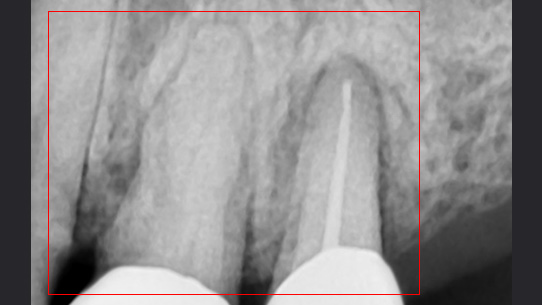

심한 염증과 기존 보철물의 오염상태가 심해 다른 병원에서 임플란트 17개 진단을 받고 내원, 특히 앞니부분의 치조골이 많이 약해져 흔들림이 심하여 바로

치주치료를 시행하였습니다. 치주치료 2주 후 앞니 잇몸이 개선되어 발치 하지 않고 교정 유지장치를 이용하여 흔들림을 보완하였습니다.

심한 염증으로 치아가 흔들리는 상태

앞니 흔들림을 보완하는 유지장치 부착